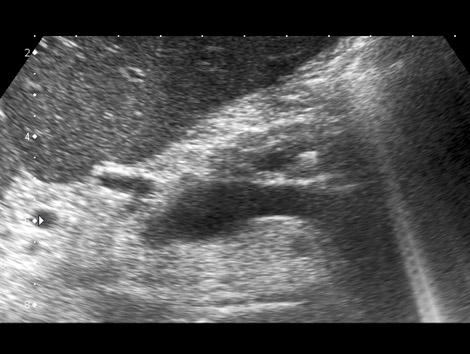

3.2. Pancreatitis crónica